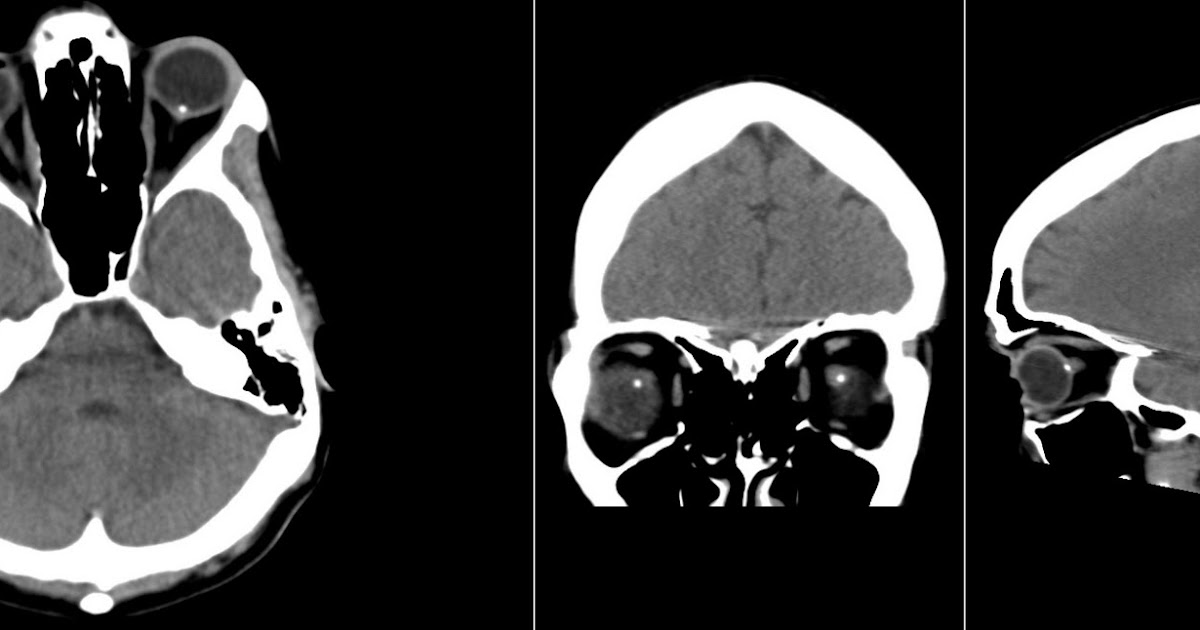

Computed tomography scan of optic nerve head showing calcification of Optic Disc Drusen Radiology Features are those of optic disc. The most accredited theory is that they. A tiny calcific spot is noted at the anatomical site of the optic disc bilaterally, no mass is seen on either side. Optic nerve drusen are refractive, calcified nodules located within the optic nerve head. Optic disc drusen (odd) are acellular deposits in the prelaminar optic nerve. Optic Disc Drusen Radiology.

CT of Optic Drusen Stock Image C043/0147 Science Photo Library Optic Disc Drusen Radiology Optic disc drusen (odd) are autofluorescent, calcified deposits found in the optic nerve head, and typically occur in small,. A tiny calcific spot is noted at the anatomical site of the optic disc bilaterally, no mass is seen on either side. If the optic disc drusen are superficial, this can aid in diagnosis during the dilated fundus exam. The most. Optic Disc Drusen Radiology.

Optic Disc Drusen Bilateral calcifications located at the site of the Optic Disc Drusen Radiology Optic disc drusen (odd) are acellular deposits in the prelaminar optic nerve head. Optic nerve drusen are refractive, calcified nodules located within the optic nerve head. A tiny calcific spot is noted at the anatomical site of the optic disc bilaterally, no mass is seen on either side. If the optic disc drusen are superficial, this can aid in diagnosis. Optic Disc Drusen Radiology.